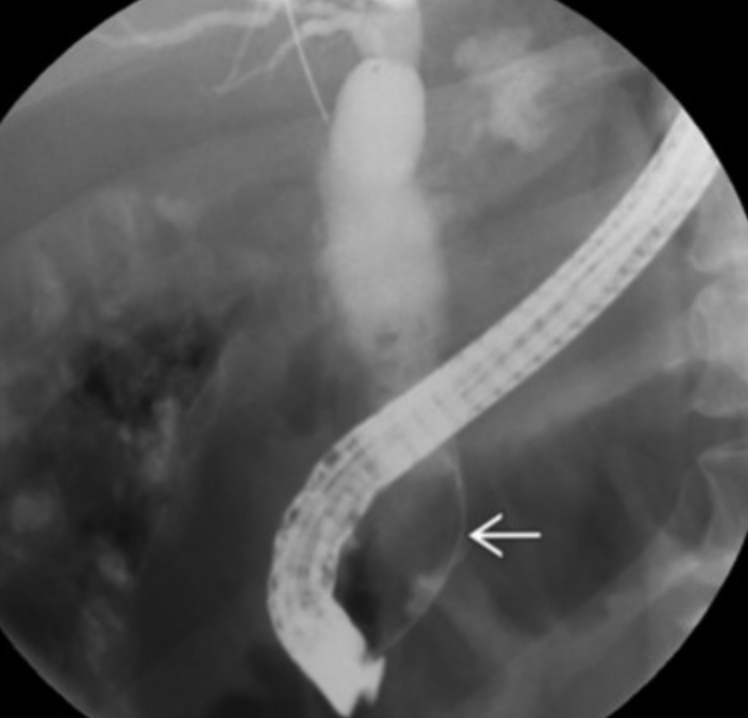

Primary Sclerosing cholangitis

• Multifocal structures of the intra and extrahepatic biliary ducts

• Increased risk for cholangiocarcinoma

• Associated with ulcerative colitis

• Findings

• US

• Biliary wall thickening

• Biliary strictures